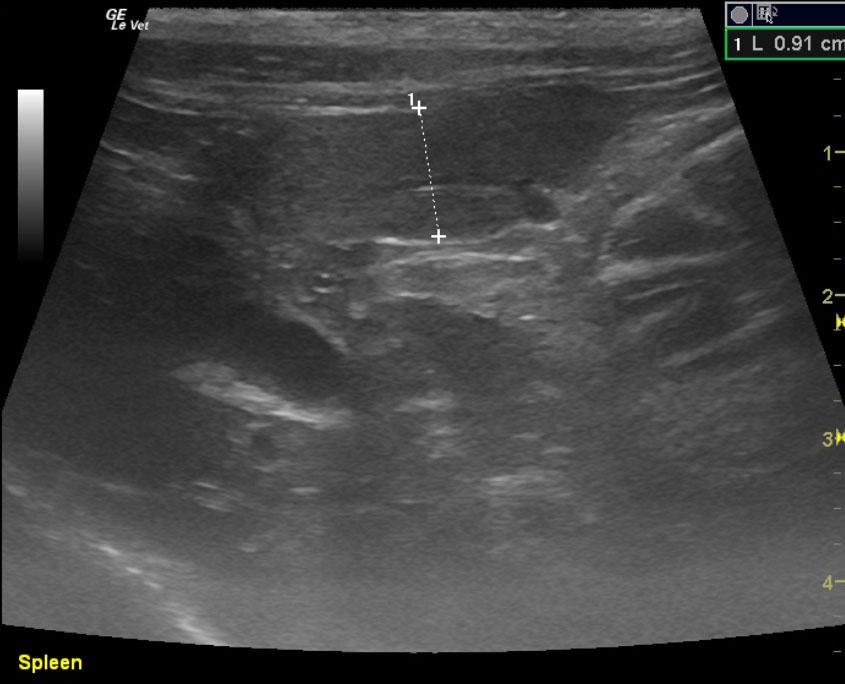

An 16 year-old NM DSH was presented for evaluation of small kidneys and an abdominal mass. Urinalysis showed an inappropriate urine specific gravity (1.014). CBC was within normal limits but elevated creatinine was present on serum biochemistry.